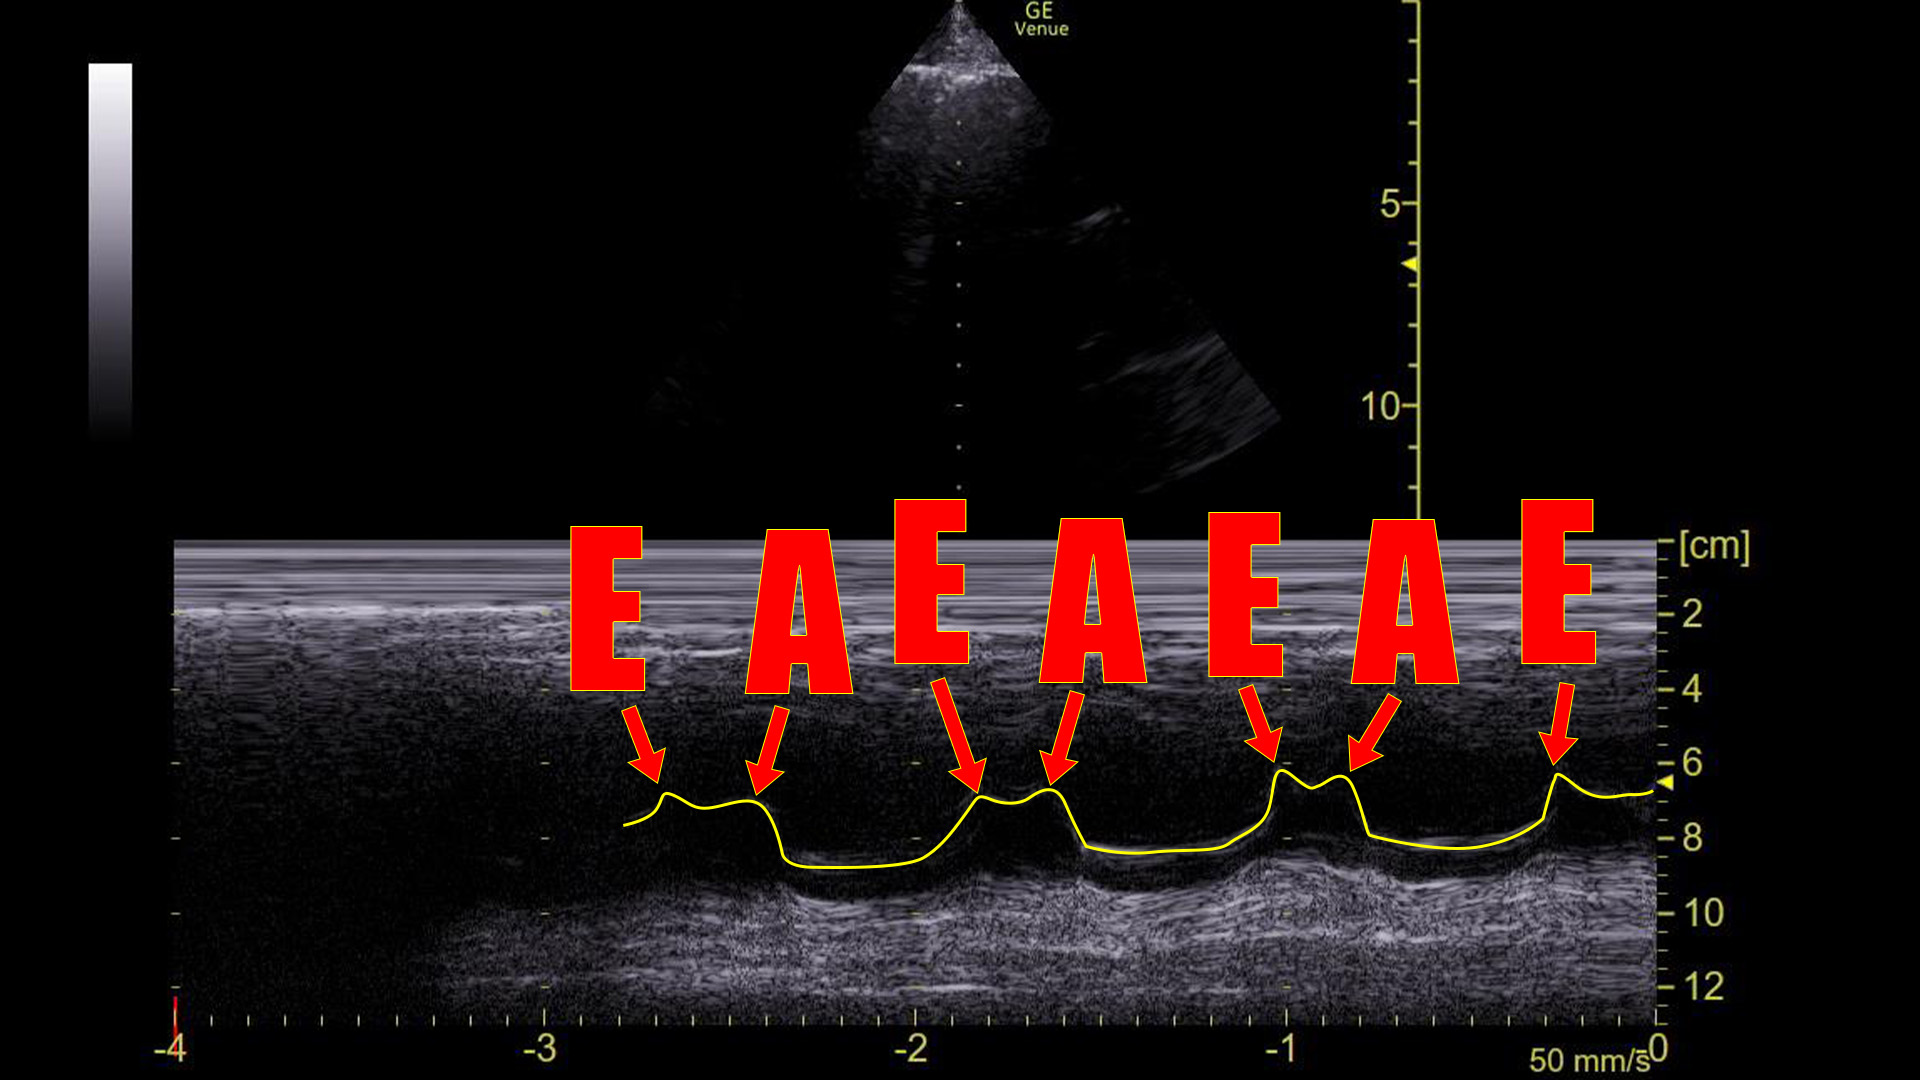

The point is, that in a sinus rhythm, the mitral valve opens not once, but twice for every contraction: Once during ventricular relaxation (passive ventricular filling) and a second time during atrial contraction.

We can see this on ultrasound as demonstrated above. Graphically on the screen, the first movement is called the E-wave, and the second is called the A-wave.

Compare that to the tracing before the cardioversion:

There are no A-waves.

This tells us that the atria are not contracting in an organized, functional way because the mitral valve is only flapping once during each heart beat.

This cannot be a sinus rhythm. However, it does not necessarily identify what the arrhythmia is. Atrial fibrillation would certainly look like this, although it would probably not be this regular. Atrial flutter with 2:1 block would look like this**. “SVT” would look this way as well as would ventricular tachycardia. The point is that the absence of A-waves at the mitral valve rules out normal atrial contractions, but does not, by itself, define a particular arrhythmia.

In a sinus rhythm, the mitral valve opens twice during ventricle filling: once during passive filling, then again during atrial contraction. We can see these two movements on an M-mode tracing with the spike placed through the anterior leaflet of the mitral valve on a parasternal long axis view of the heart. Graphically, the first movement produces a wave that is termed the E-wave; the second is the A-wave. Absence of the A-wave tells us that there is no atrial contraction, which would be seen in conditions like atrial fibrillation, SVT, atrial flutter, or ventricular rhythms.